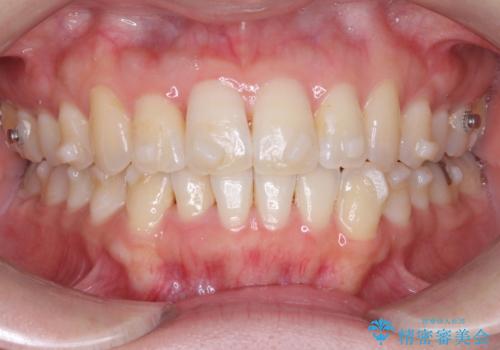

【インビザライン】前歯の凸凹をなおしたい

- 前歯の凸凹を主訴に来院されました。

上顎の急速拡大を行なったのちインビザラインにて治療を行なっております。

今回のケースは後戻りのリスクを低くし、またディスキング量を減らすために上顎の急速拡大を行なっております。